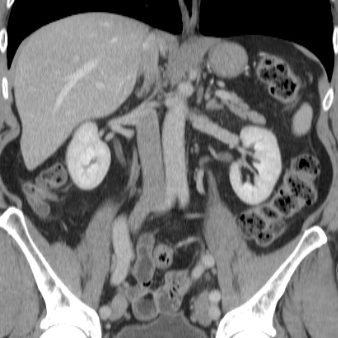

Abdomen

Coronal